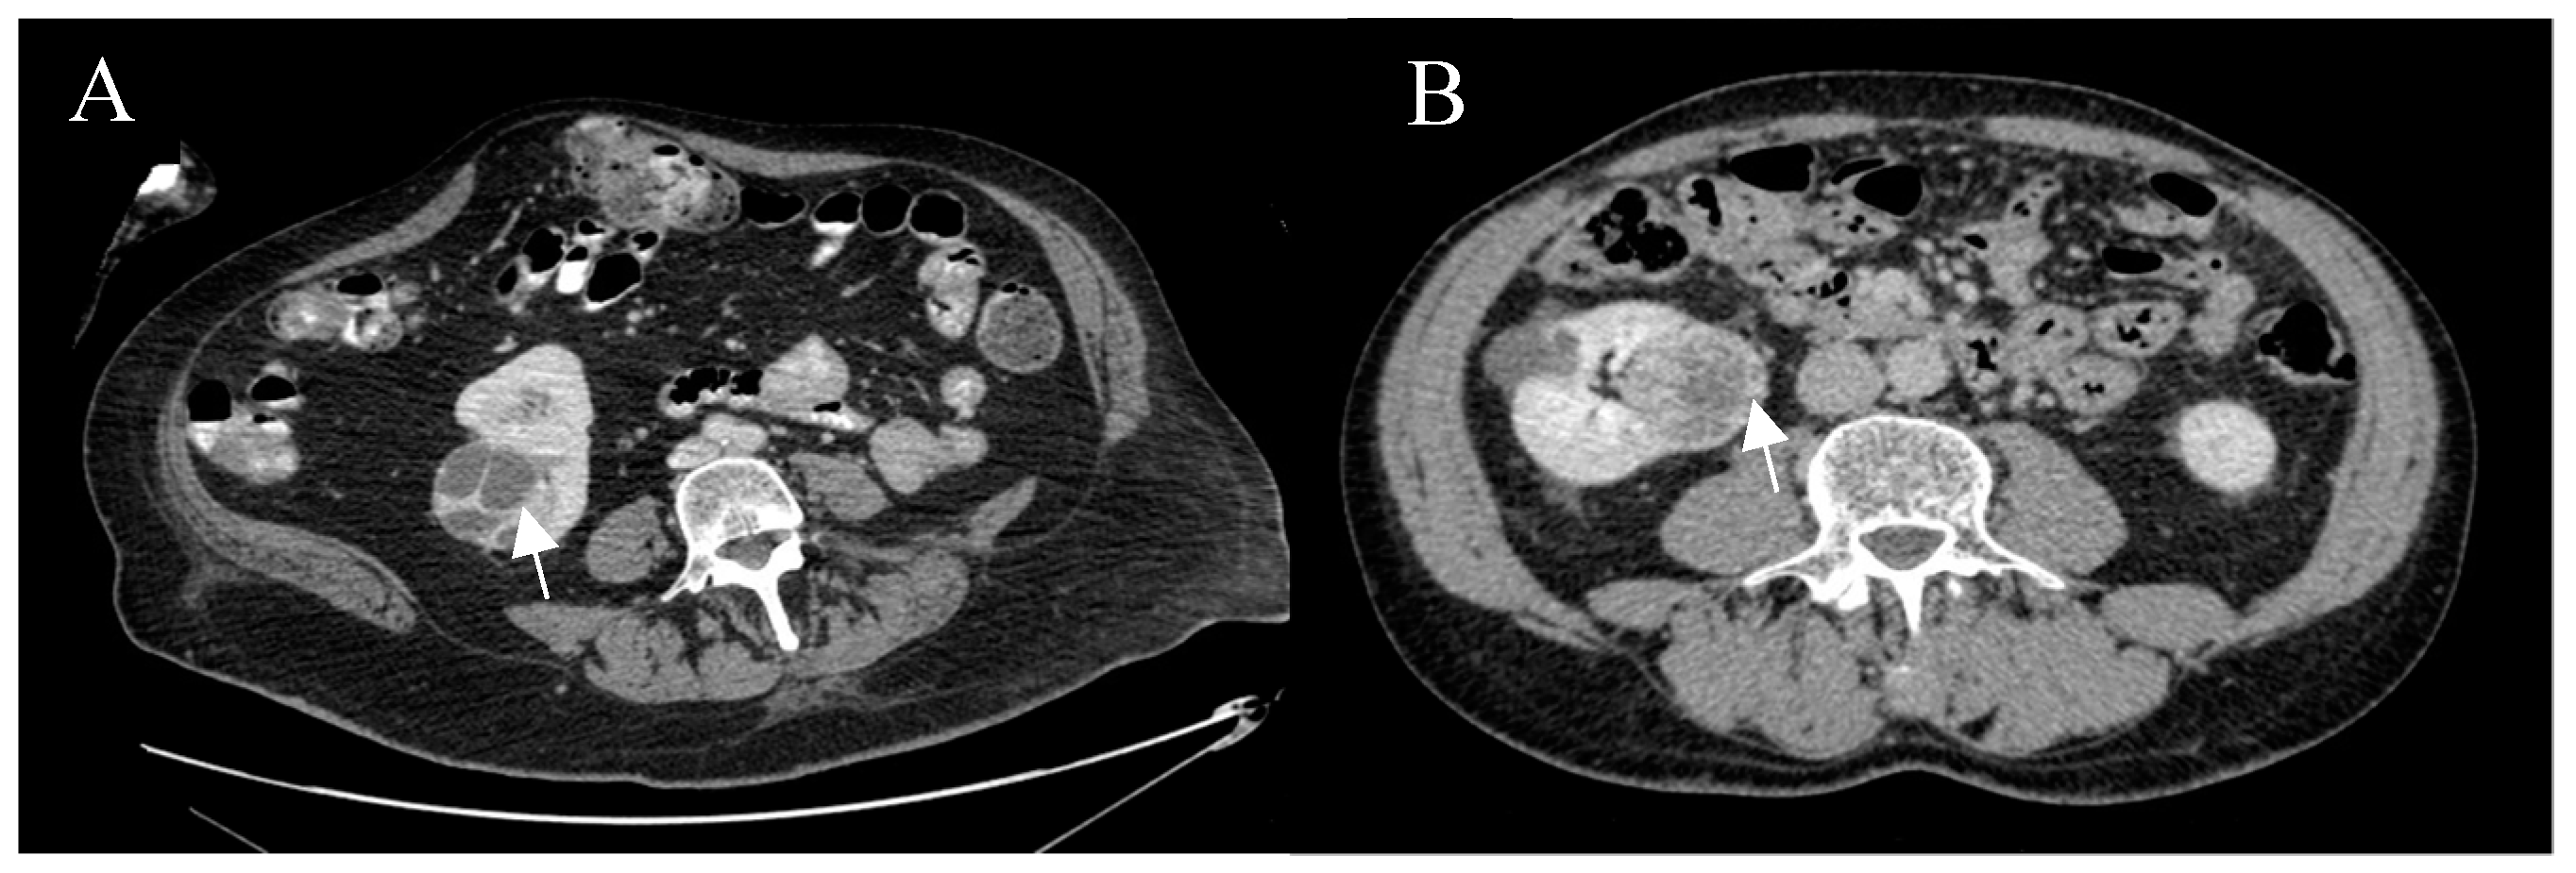

4.4. Imaging Protocol